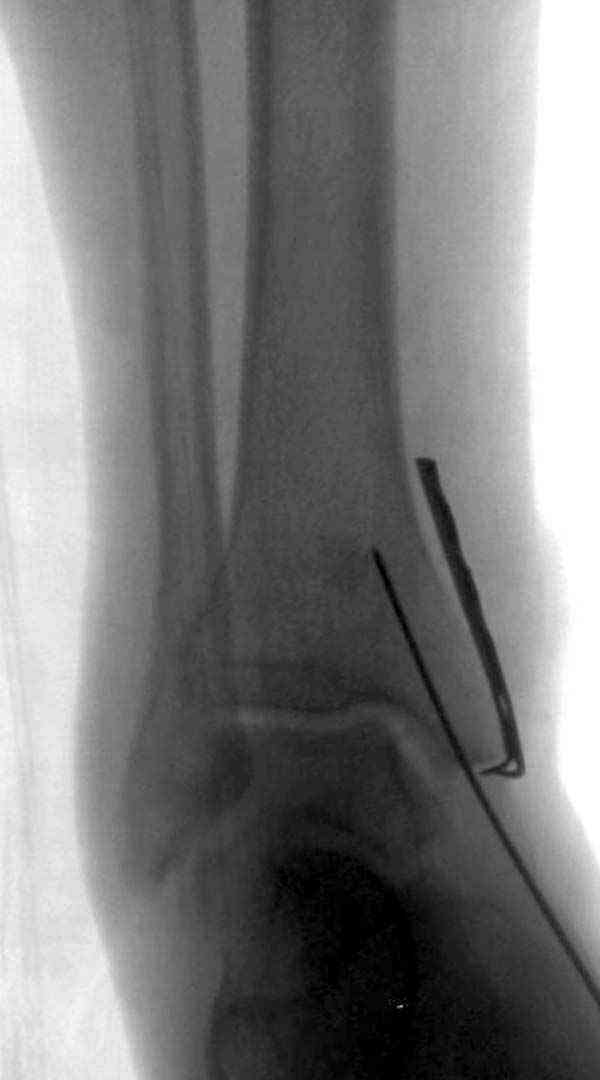

Нет первичных снимков, перелом очень низкий и под большим сомнением диагноз разрыва синдесмоза. Медиальная сторона отрепонирована на "хорошо" и, по-видимому, прорезание проволоки произошло во время операции. Без снимков трудно судить о высоте малоберцовой, а лодыжка находится в варусе. Лагирование получилось, но возле тонких шурупов передне-задний шуруп выглядит немного тяжеловато.

Здесь несколько частных случаев: перелом голеностопа со сравнительными снимками и разрыв синдесмоза, а также медиальная Hook пластина.